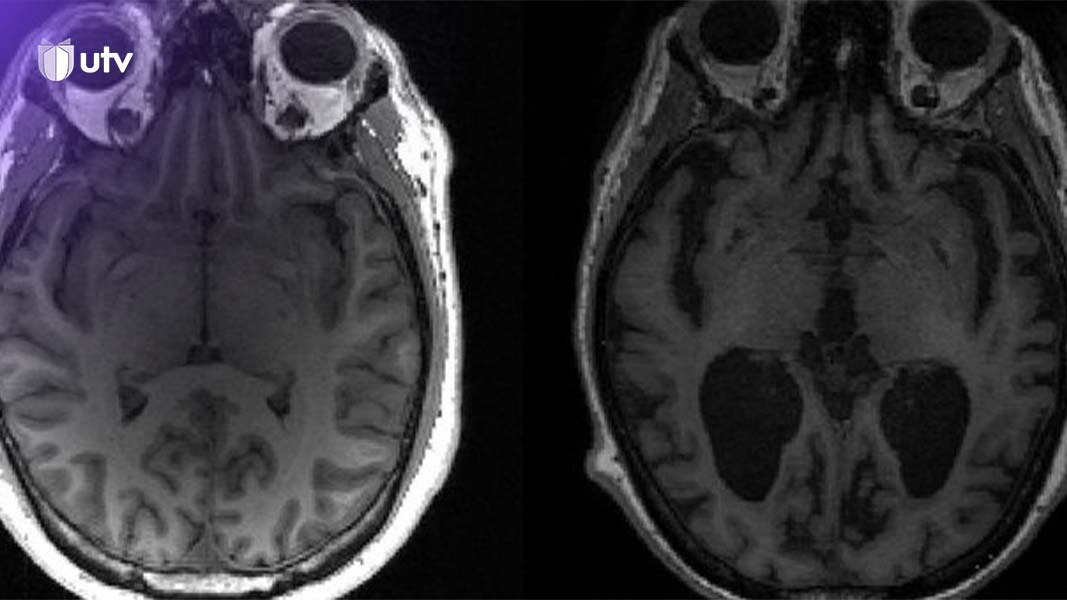

دراسة طبية: وجود فيروسات معينة في جسم الإنسان يمكنها تحفيز مرض الزهايمر

قالت دراسة في مجلة “مرض الزهايمر”، إن هناك أدلة جديدة على أن وجود فيروسين شائعين في نفس الوقت، يمكن أن يسببا مرض الزهايمر لدى المصاب بهما.

وأكدت الدراسة، أن الفيروسات المسؤولة عن جدري الماء والهربس، يمكن أن يتسببا معاً في مرض الزهايمر.

ويقول الباحثون في جامعة تافتس، في أميركا، وجامعة أكسفورد في بريطانيا، إنهم أثبتوا أن وجود فيروسين جنباً إلى جنب، يمكن أن يعزز فائضاً من البروتينات المسؤولة عن لويحات الدماغ المميزة لمرض الزهايمر.